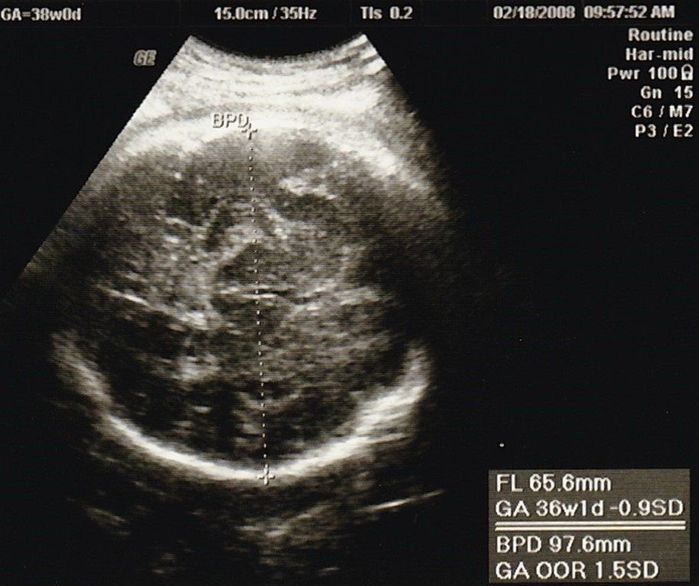

妊娠37週目のエコー写真

推定体重3000gにまで増えていてビックリ。私自身が2600gで生まれており、「お産は母親に似る」と聞いていたので、勝手に少し小さめで生まれてくると思っていました。「4000g超えになるかも」と不安を覚えました。私は既に10kg近く増加になっていたので、この時期から意識的に散歩と、食べすぎに気をつけ、臨月は赤ちゃんの増加分(約1kg)にとどめ、最終的に10.5kg増で抑えました。